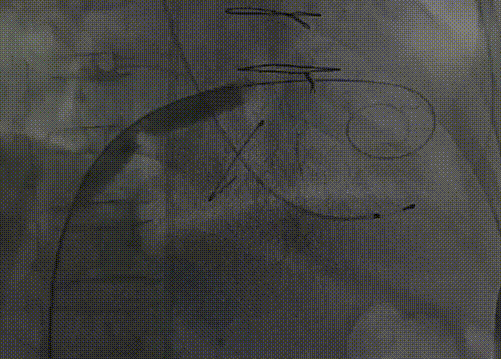

经股动脉入路,抓捕器捕获左室-升主动脉导丝,建立股静脉-右房-左房-左室-主动脉-股动脉轨道;

捕获器获取导丝,建立通路

第一次尝试穿瓣周过去,无法对二尖瓣前叶进行切割,只能拉到后叶,没有盲目操作,退出导丝导管重新跨瓣,再次建立轨道,造影和超声下确认导丝位置位于前瓣叶处;

导丝重新跨瓣,捕获器再次获取导丝建立通路